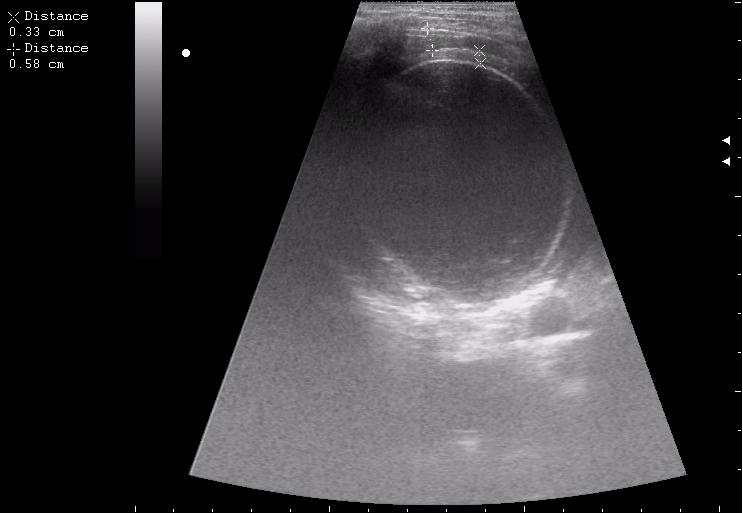

17-летняя девушка с множественными поражениями печени

нагноение остаточной полости